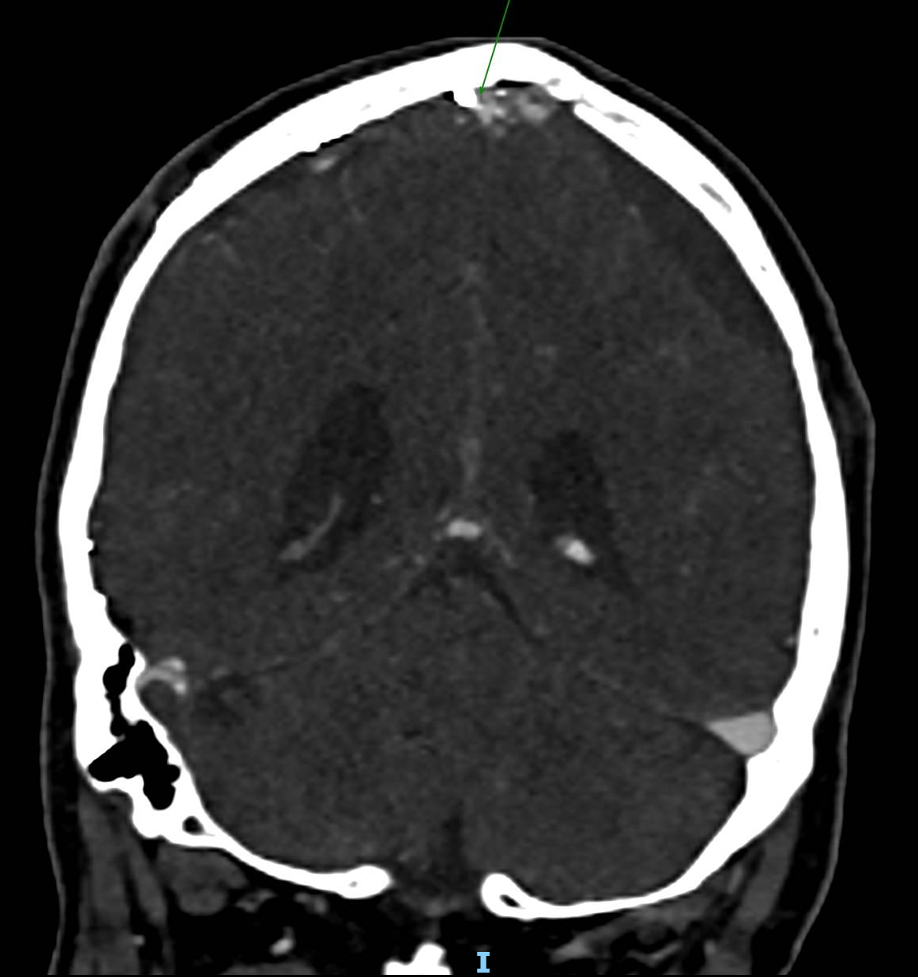

Case Summary: In less than 400 words, please summarize the case. Briefly describe the case and any particular complexities and/or complications encountered.: A 77-year-old male initially presented to our hospital after a fall with bilateral frontal contusions, traumatic subarachnoid hemorrhage, and bilateral subdural hematomas (SDH). Approximately one month later, he re-presented with altered mental status, confusion, staring spells and bilateral jerking of his lower extremities concerning for seizure activity found to have worsening bilateral chronic subdural hematomas with mass effect. He underwent hematoma evacuation with bilateral burr holes and middle meningeal artery (MMA) Onyx embolization. Three weeks later, he re-presented with generalized tonic-clonic seizures, found to have an acute intraparenchymal hemorrhage and extensive cerebral venous sinus thromboses (CVST) with embolization material seen in the transverse and superior sagittal sinuses on CT Venogram.

There are currently no specific guidelines for chronic SDH management, although MMA embolization is becoming a more widely used procedure. Our case report provides a novel description of CVST secondary to migration of the Onyx material into the dural venous sinuses after Onyx embolization for subdural hematoma that has not previously been described in the literature. This case highlights a potential complication of MMA embolization with embolization material getting into the venous system, and warrants further discussion on whether anticoagulation would be beneficial for this complication. This case also provides forum for discussion on the unique management of CVST, intraparenchymal hemorrhage, and chronic SDH.